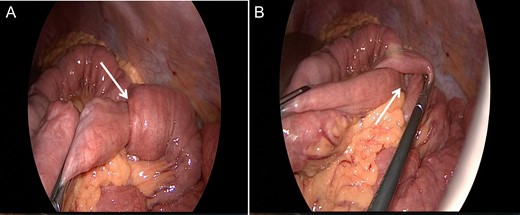

We present the case of a 30-year-old male patient who was admitted to our emergency department with a 24 h history of severe abdominal pain, diarrhea and vomiting. During clinical examination, the patient reported mentioned an episode with identical symptoms three months before that was treated conservatively at another institution. The patient’s past medical history included posttraumatic stress disorder and chronic consumption of cannabis via inhalation (10–15 joints a day). The pain intensity was so strong that the patient was observed by his girl-friend to sluice boiling water on his body. In the hospital at admission the patient was aggressive and endangered himself and others. The blood test demonstrated an increased leucocyte count with 16.88 G/l, but a normal C-reactive protein level with 0.1 mg/dl. At first, the patient was treated with lorazepame and olanzapine under clinical suspicion of acute psychosis related to his cannabis consumption. Due to further exacerbation of the pain, a CT scan was performed showing several small bowel intussusceptions in the left abdominal region (Fig. 1A and 1B). Because of the acute abdominal symptoms and the findings in the CT scan a diagnostic laparoscopy was performed. Intraoperatively numerous, at least ten, regions of jejuno-jejunal intussusceptions were found (Fig. 2A, Video 1). The intussuscepted jejunal segments were repositions by careful stretching of the small bowel. During examination of the affected bowel segments there was no evidence of a tumorous lesions or any other pathology (Fig. 2B). Only the intestinal content appeared thickened and pasty. Most interestingly severe atony of the whole small bowel was observed (Fig. 2A, Video 1). Because no ischemic leasions or other pathology was found, no intestinal resections deemed necessary and the operation was terminated. The patient developed no surgical complications, and had bowel movements after gastrografin application. Due to a good recovery, he was discharged on postoperative Day 2 with recommendation of adequate liquid intake and use of laxatives on demand.

Diagnostic laparoscopy showing multiple intussusceptions (arrow) without any further pathologic findings.